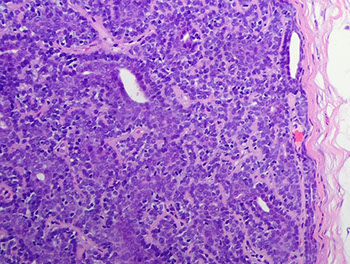

Merkel cell carcinoma

MCC

Merkel cell carcinoma (MCC)

- aka primary NE carcinoma of skin, trabecular carcinoma

Uncommon, aggressive cutaneous tumor that usually present on the head and neck of elderly pts in areas of sun damaged skin

- clinically are painless dermal nodules that are erythematous or violaceous (delayed dx since no sx)

- 80% of MCC are assoc c Merkel cell polyomavirus (MCPyV)

*** DDx for small round blue cell tumors in skin: blue LEMONS *** Lymphoma, Ewings sarcina, Merkel cell ca / melanoma, Oat cell ca of lung, Neuroblastoma, Small cell endrocrine carcinoma***

Micro: small round blue cells close together c little cytoplasm c molding, apoptotic cells and mits

- can have intraepidermal growth similar to melanoma

IHC: (+) synapto, chromogranin, NSE, CK20 (in dot-like perinuclear pattern), Neurofilament (8/8), AE1/AE3, Cam5.2, Merkel-cell polyomavirus

- neg: TTF-1

EM: membrane-bound dense core granules

Px: Worse if p63+; commonly recurs and mets, assoc c high mortality

More merkel cell ca